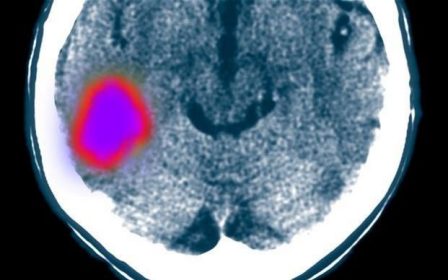

پس از سكته، مغز قابليت خودترميمي دارد

محققان سوئدي با استناد به يك مطالعه جديد روي موش ها گفتند كه استفاده از دارو براي درمان التهاب پس از سكته مغزي احتمالا مي تواند به روند بهبود آسيب برساند.

پزشكان مدتها معتقد بودند كه التهاب در ناحيه آسيب ديده مغز لازم است هر چه سريعتر با دارو كنترل شود.

اما اكنون محققان مي گويند كه مغز قابليت خود ترميمي نواحي آسيب ديده را دارد و جلوگيري از طي شدن اين روند، مي تواند از بهبودي كامل مغز جلوگيري كند.

دكتر زال كوكيا از دانشگاه لوند سوئد مي گويد: نتايج مطالعه جديد با باورهاي قبلي ما كاملا منافات دارد و داده ها نشان مي دهد كه سيستم ايمني مي تواند در بهبود طولاني مدت عملكرد مغز پس از سكته نقش مهمي داشته باشد. به واقع، جلوگيري از التهاب ناشي از سكته مغزي بدون در نظر گرفتن پويايي و مشخصات واكنش ايمني مغز مي تواند در بازيابي مغز پس از سكته مغزي زيان آور باشد.

وقتي سكته مغزي اتفاق مي افتد، سلول هاي عصبي در ناحيه آسيب ديده مغز مي ميرند و التهابي را ايجاد مي كنند كه در نتيجه آن، سلول ها سيستم ايمني بدن از جمله مونوسيت ها جذب مي شوند.